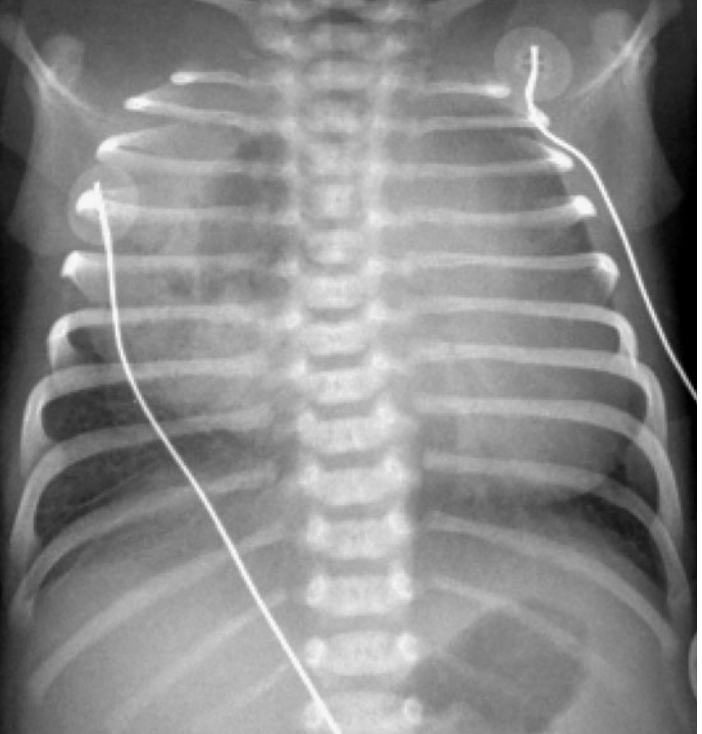

Congenital cystic adenomatoid malformation (CCAM)

path: thought to arise from an embryonic disruption before the thirty-fifth day that causes improper development of bronchioles.

symptoms: The infant has diminished breath sounds on the left, and the PMI is shifted toward the right.

diagnosis:

The cystic mass is usually identified on prenatal ultrasound around the 20th week.

Large lesions (as that noted on the radiograph on the right side) may compress the affected lung and cause pulmonary hypoplasia, which may cause midline shift away from the lesion (note the heart is shifted toward the left on the radiograph).

treatment: Treatment is typically surgical excision of the affected lobe. Some patients may be at risk for primary pulmonary malignancy.,